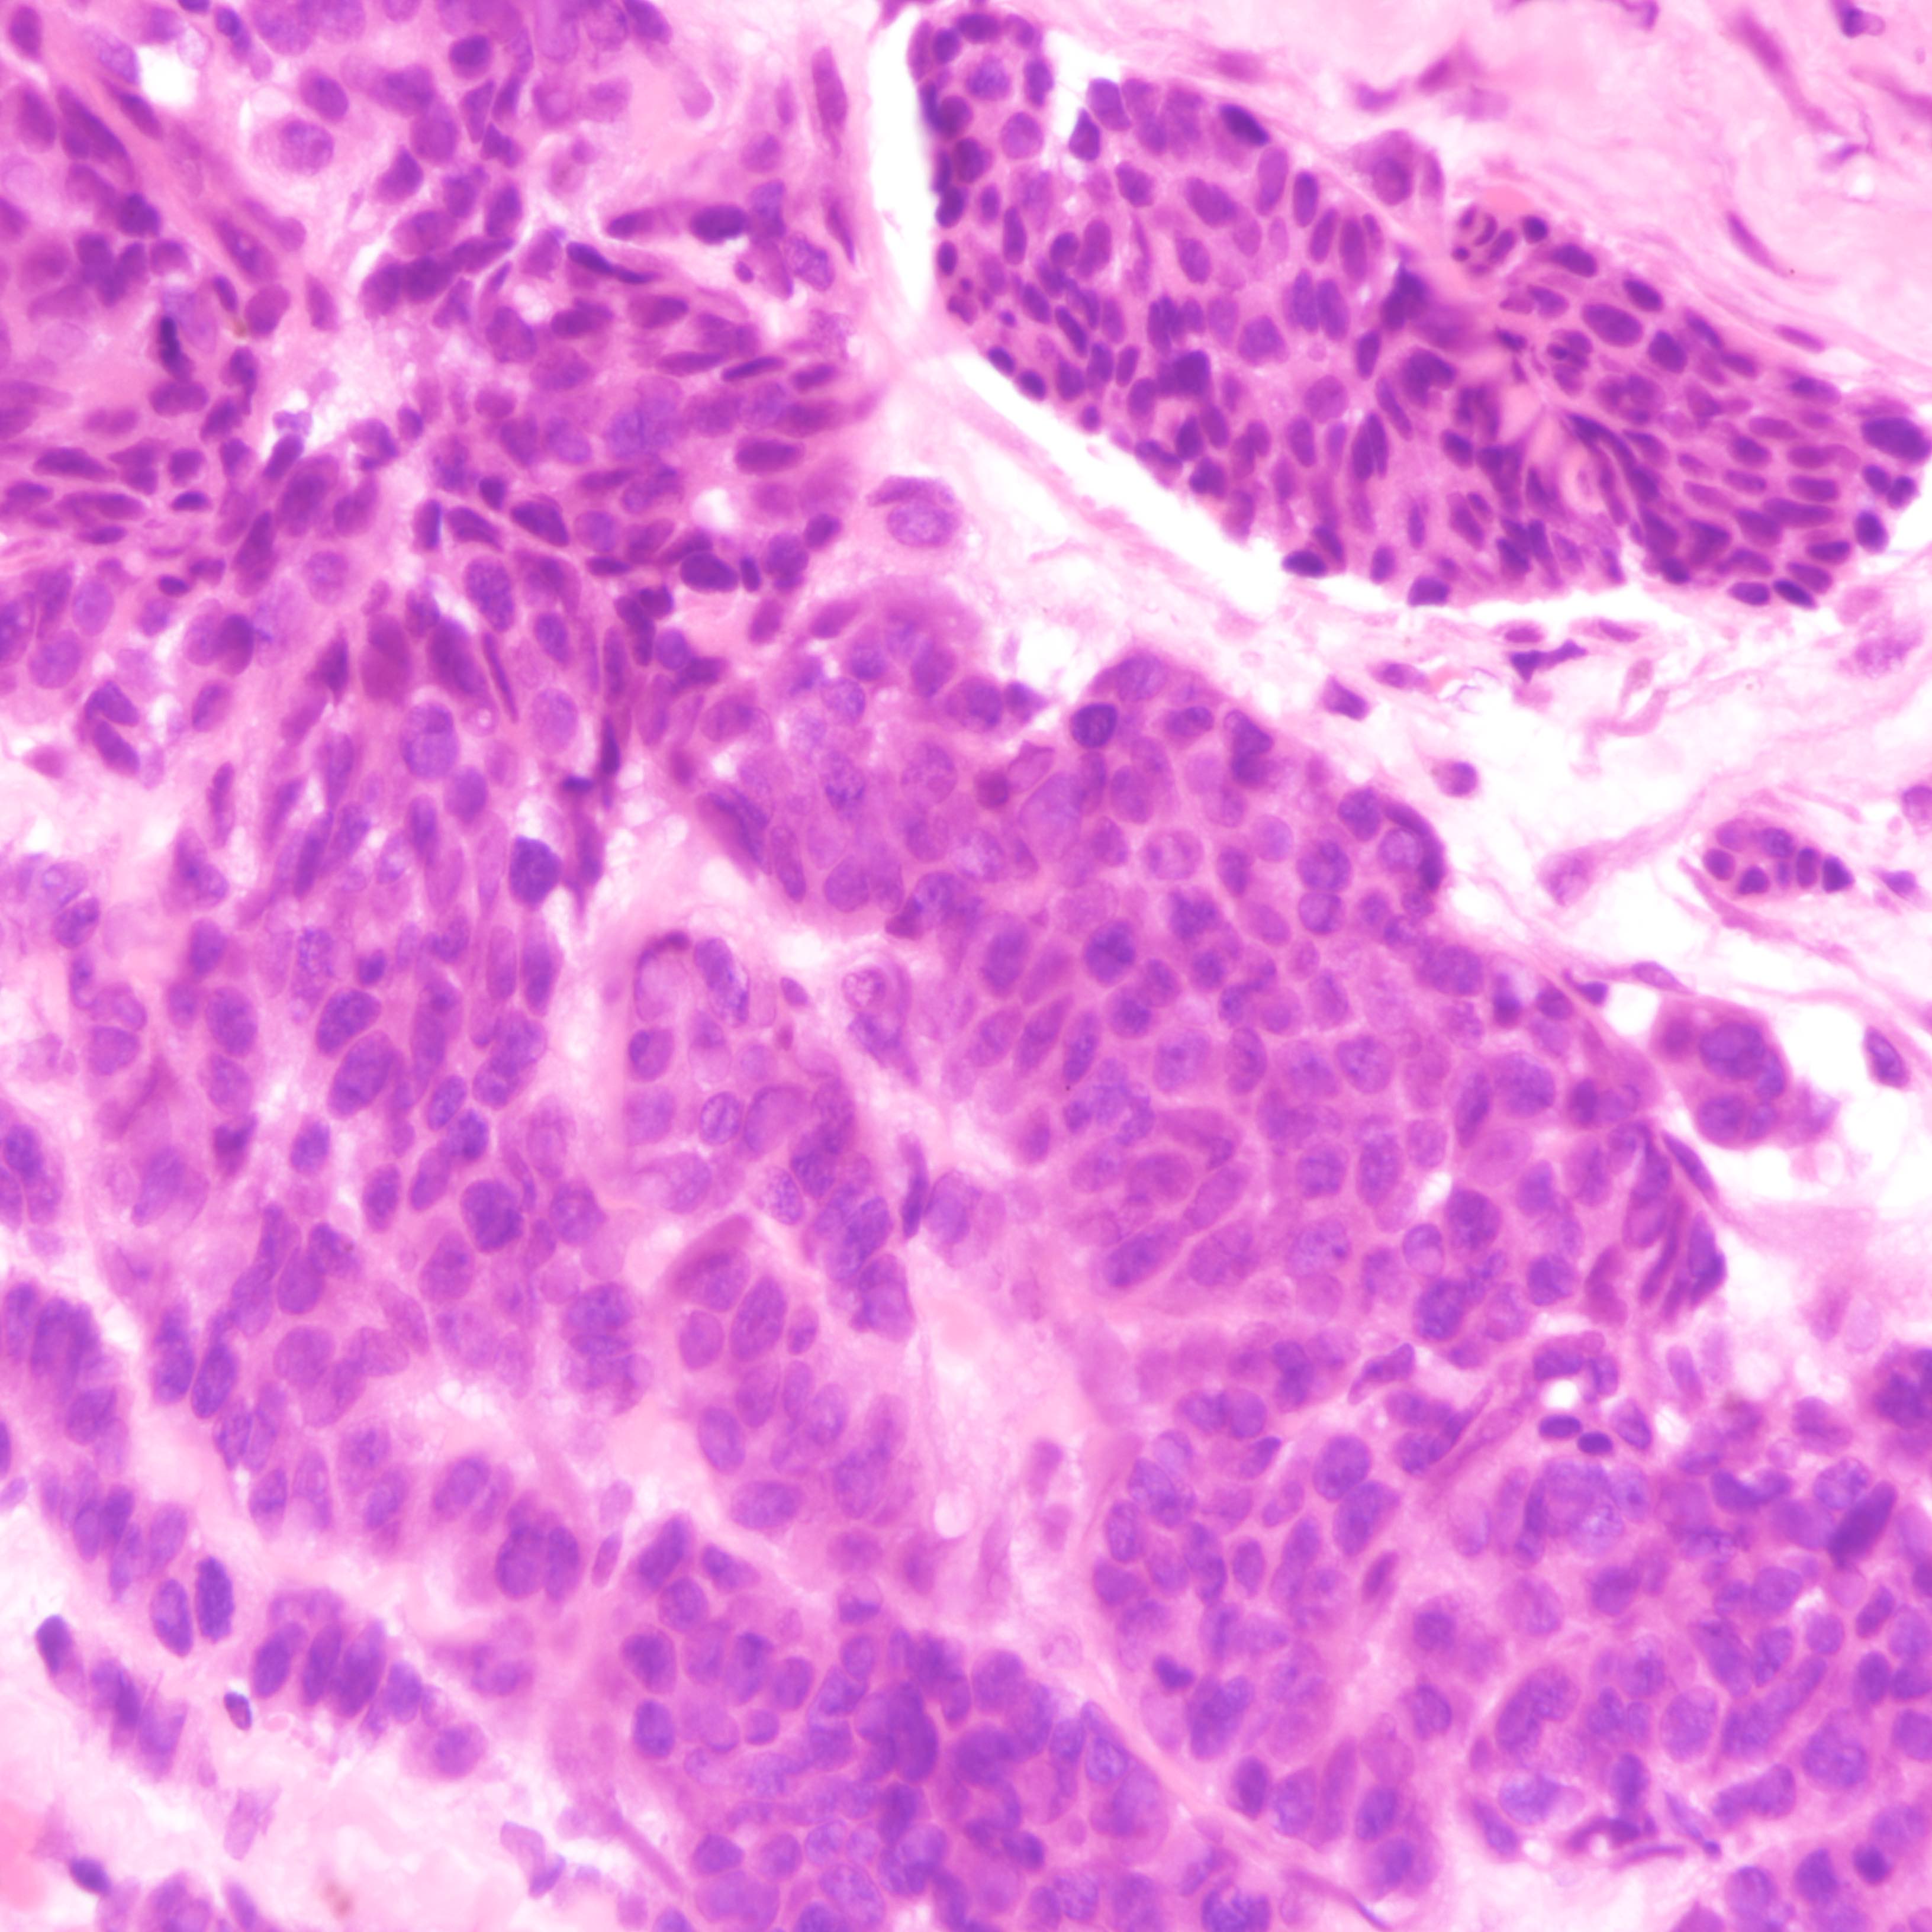

Contributed by Joshua J.X. Li, M.B.Ch.B., Gary M. Tse, M.B.B.S. and Kristen E. Muller D.O.

Small cell carcinoma

- Small cell carcinoma:

- Infiltrative growth pattern

- Crush artifact frequent

- Necrosis and lymphovascular invasion common

- Tumor cells densely packed with ill defined cell borders

- High N/C ratio with scanty cytoplasm

- Small dark hyperchromatic nuclei and inconspicuous nucleoli

- Mitotic count high

- Associated with proliferative changes, in situ carcinomas and invasive carcinomas (Am J Surg Pathol 2000;24:1231)

- In situ small cell carcinoma present in 5 out of 9 cases in a case series

- In situ / invasive ductal, lobular and squamous neoplastic components occasionally identified

- Infiltrative growth pattern